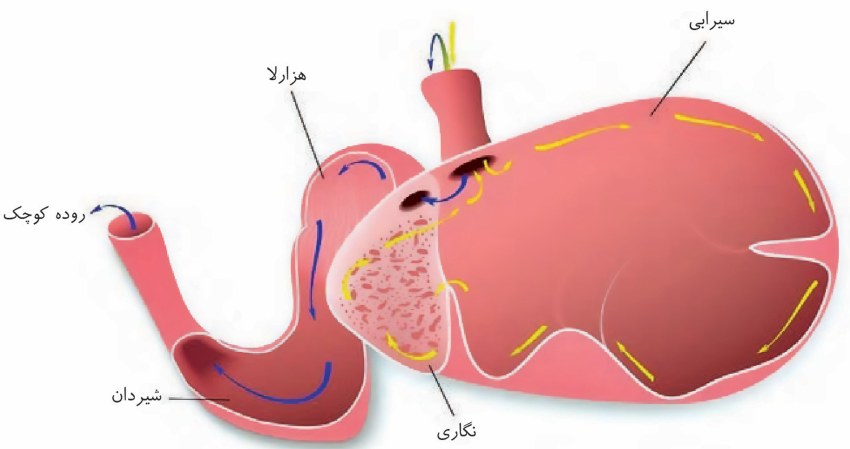

در سطح جلویی کلیه راست بخشی از کبد و کولون بالارو و در سطح جلویی کلیه چپ بخشی از لوزالمعده و کولون پایینرو قرار دارد.

۳-نیمه راست کولون افقی پایینتر از نیمه چپ آن باشد.